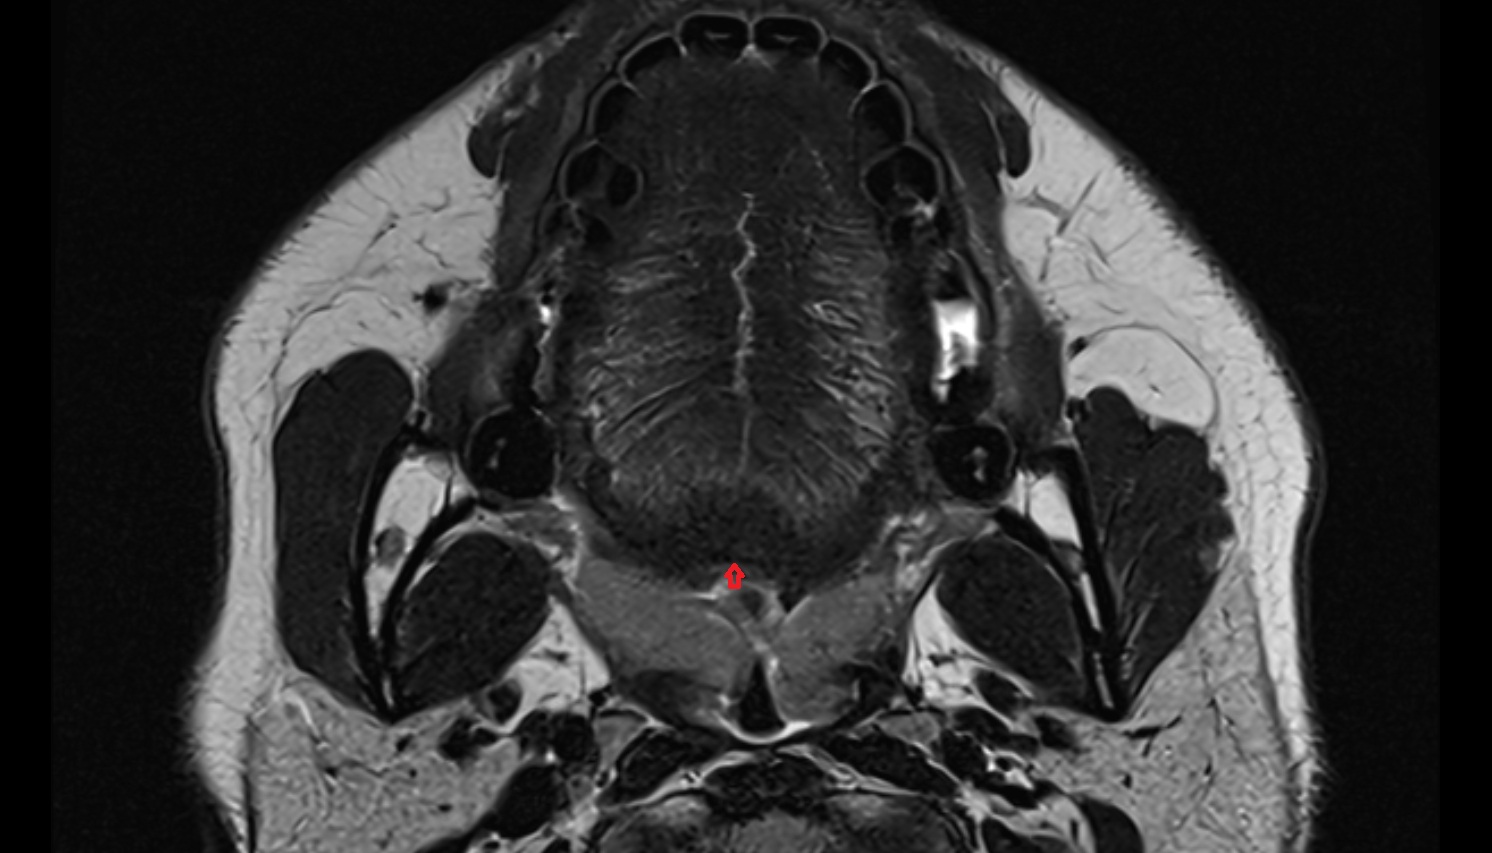

- Temporomandibular joint

- Mandibular condyle

- Mandibular fossa

- Superior head of lateral pterygoid muscle

- Inferior head of lateral pterygoid muscle

- Lateral pterygoid muscle

- Masseter muscle

- Medial pterygoid muscle

- Temporalis muscle